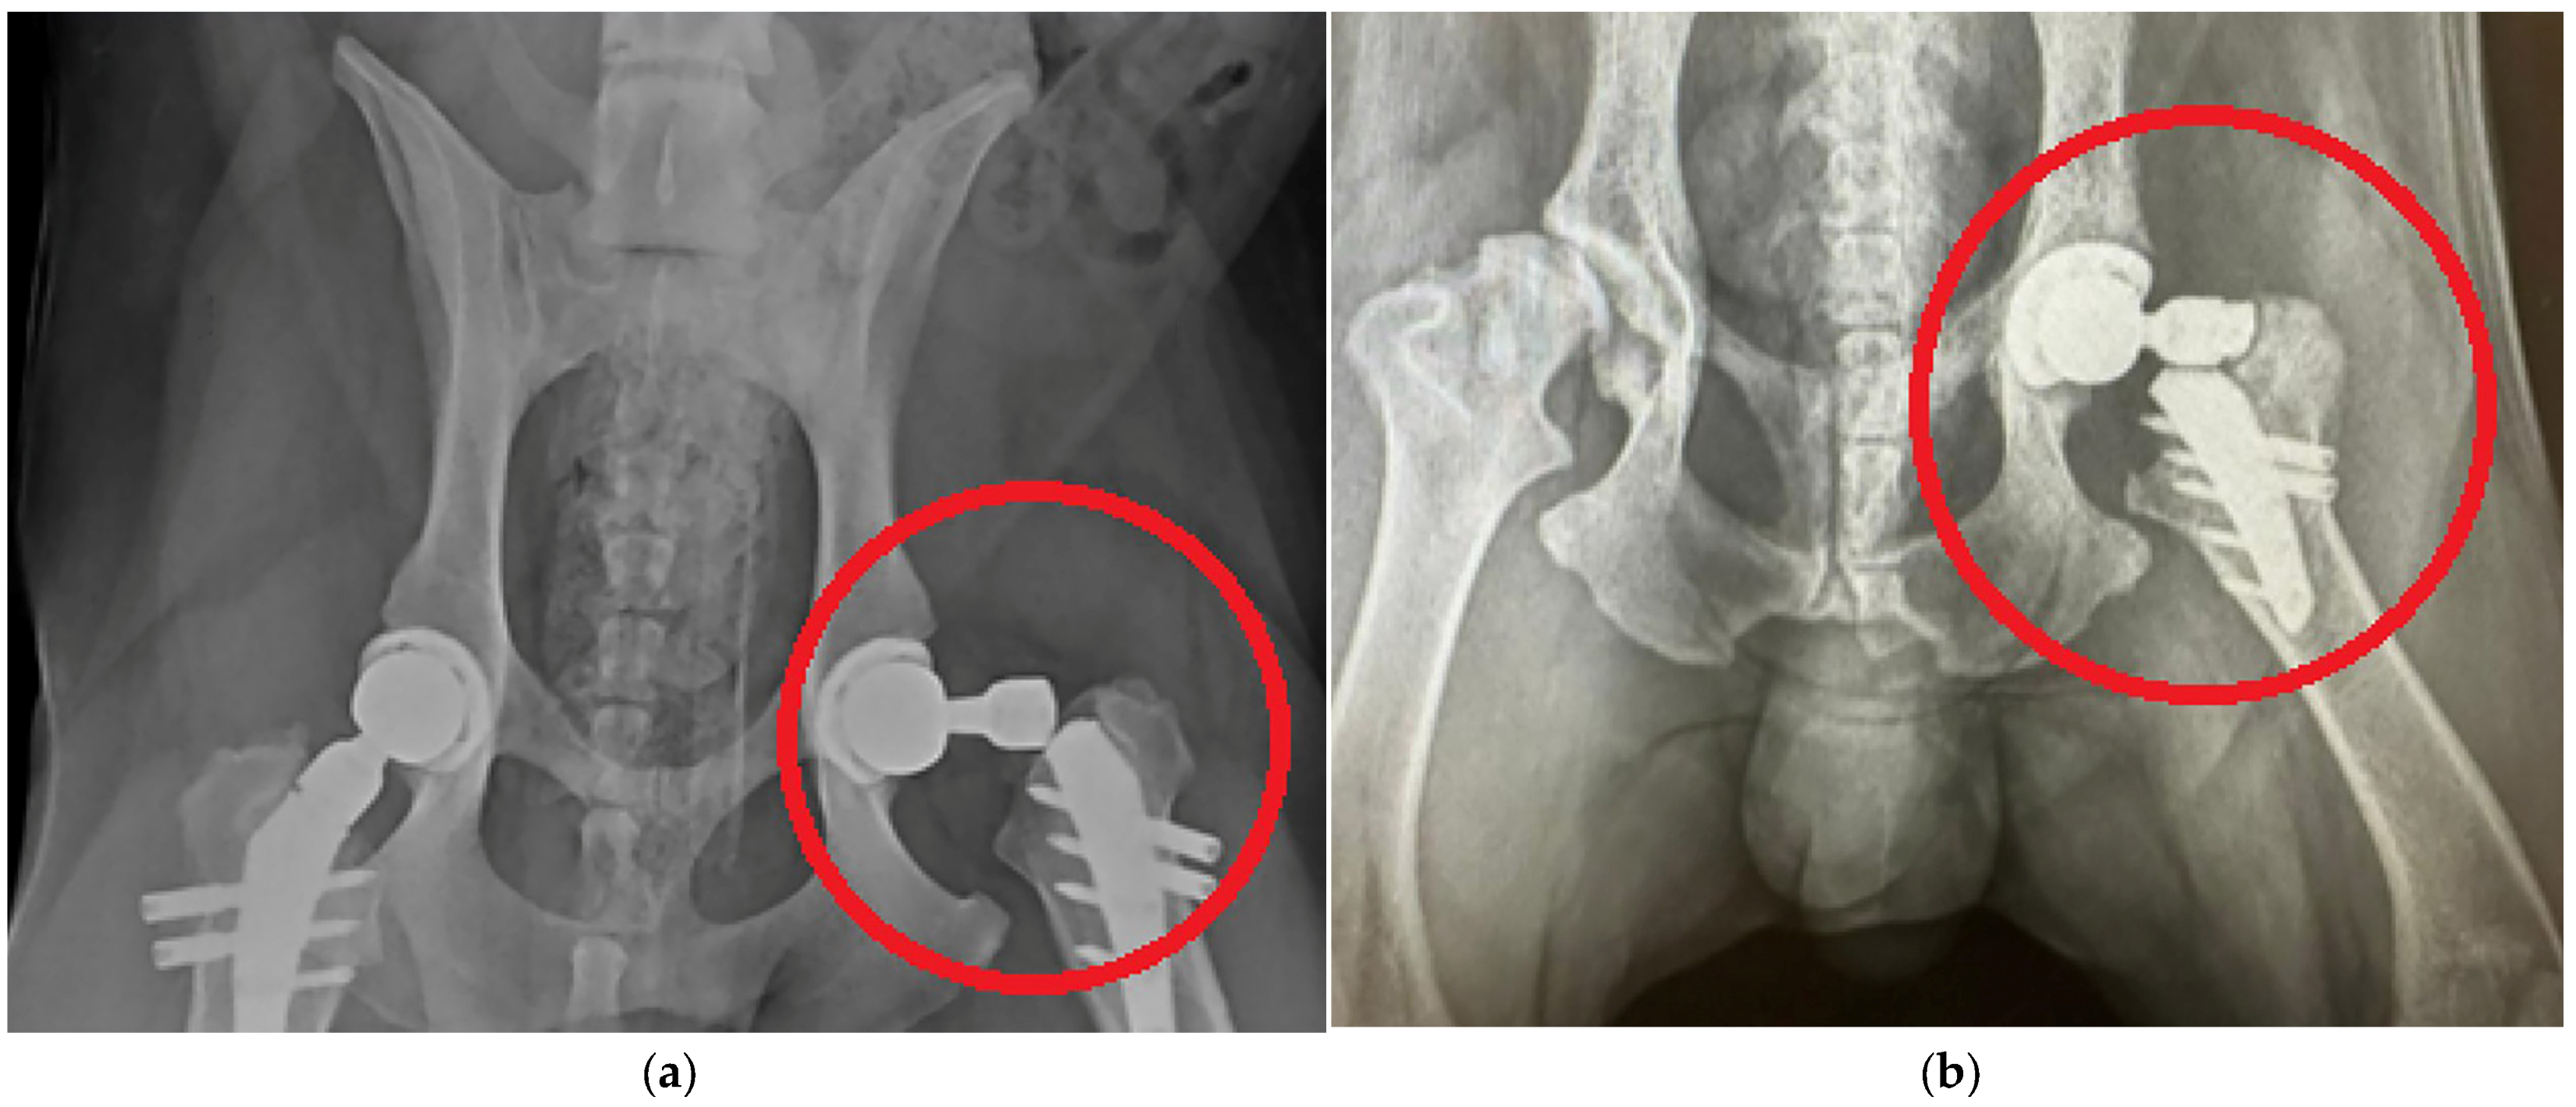

- The stem is inserted into the bone tissue without the use of adhesive cement; over time, the bone tissue “grows” around the prosthesis and provides a strong bond. Additionally, fixation with bicortical screws can be used.

- V@Art Cementless Hip Replacement System for Animals. [Electronic Resource]. Available online: https://v-art.info/ (accessed on 16 March 2025).